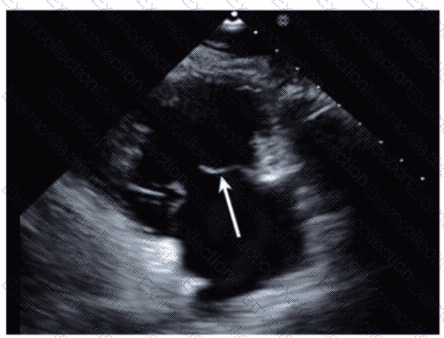

Which anatomic structure is represented by the arrow on this image?